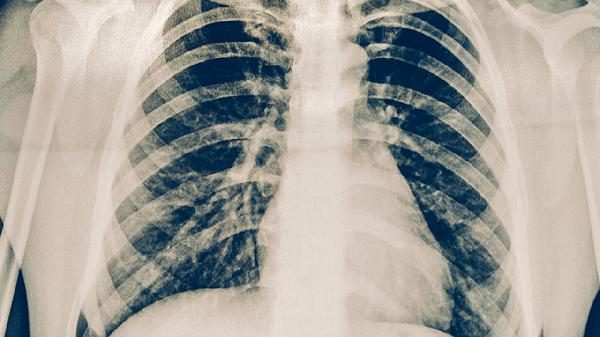

肺癌位于气管旁多数情况下可以手术切除,具体需评估肿瘤大小、侵犯范围及患者心肺功能。手术可行性主要取决于肿瘤与气管的解剖关系、是否存在淋巴结转移、患者基础疾病情况、肺功能储备以及手术团队经验。

术后需保留足够肺组织维持氧合。第一秒用力呼气容积低于1.5升或弥散功能小于40%者,手术风险显著增加。合并严重冠心病或肺动脉高压患者需多学科评估。